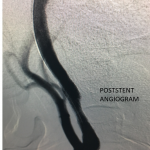

Figure 4.

Catheter angiography prior to angioplasty revealed critical stenosis (Figure 2). Angioplasty was therefore performed under local anesthesia with an embolic protection device deployed to catch any dislodged debris (Figure 3). After angioplasty, a stent was opened across the lesion to maintain long-term patency (Figure 4). Post-stent angiography showed smooth dilatation of the lesion. The patient’s aphasia continued to improve at his 6-week follow-up visit and duplex revealed no significant stenosis through the stent.